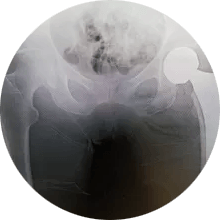

Hip and Knee Surgery in theFox Valley

A fellowship trained, board certified, orthopaedic surgeon you can count on.